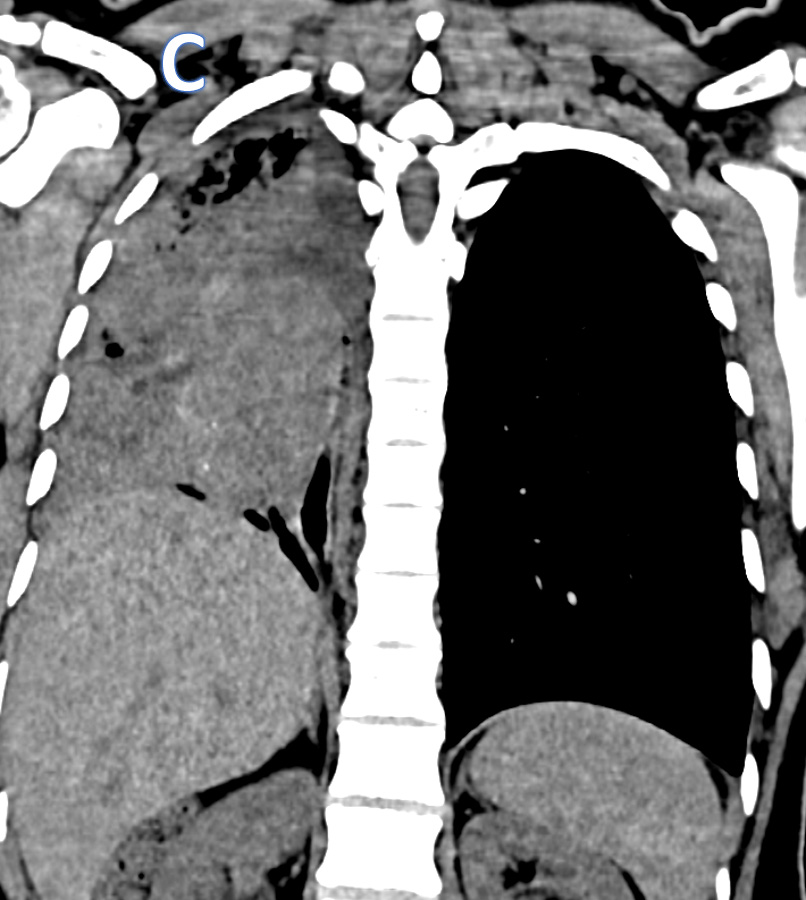

D – Axial CT Thorax

• ARROW:  Isodense mass lesion with peripheral calcific specks and endobronchial extension.

• STAR: Organised / Clotted - Hemorrhagic contents in the right hemithorax.